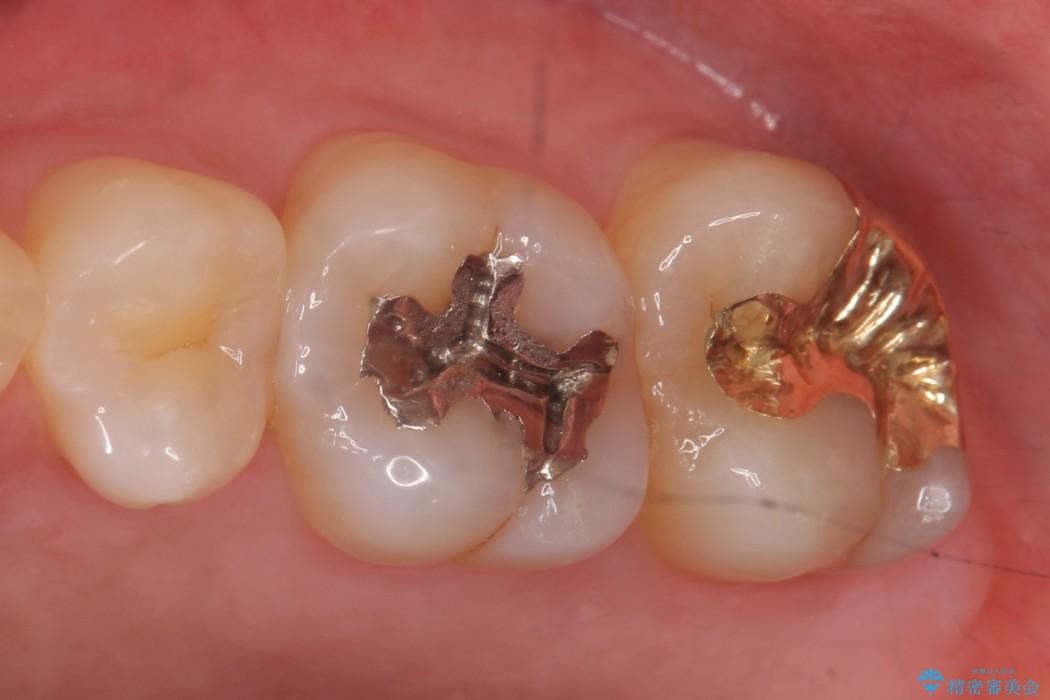

今回は一番奥の歯という位置と、噛み合わせ、清掃状態を加味して適合の高く長持ちするゴールドインレーにて治療することとしました。

ゴールドインレー

ゴールドインレーはセラミックより強度高く、使用される金合金や白金加金は汚れの付きにくいという特徴を持っており、耐用年数が長いことが特徴としてあります。特に奥歯など強く力が欠けられる箇所に適しています。

反対にデメリットして金属であるため審美性に欠けるという点があります。